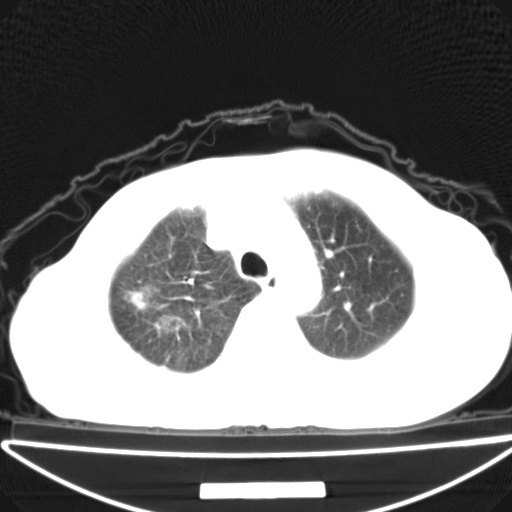

以下是引用jsgdoctor在2008-11-6 22:12:00的发言:[br]右主支气管壁明显增厚,管腔狭窄.考虑为右侧中央型肺癌伴阻塞性炎症\\肺脓肿.

以下是引用zjzjr在2008-11-6 20:25:00的发言:[br]中心型肺ca,合并阻塞性肺炎

以下是引用zsl6918在2008-11-6 19:43:00的发言:[br]右侧中心性肺癌(鳞癌)